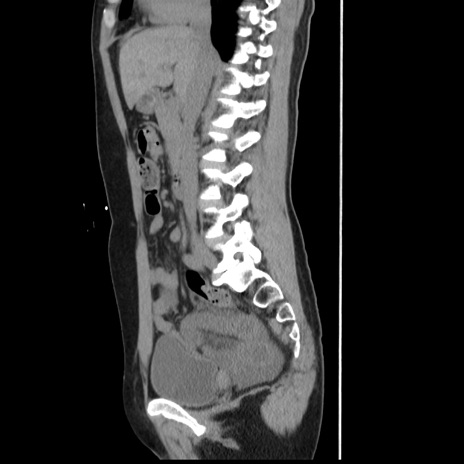

症例

【症例】 50歳代女性

【主訴】 腹痛

【現病歴】前日生レバーを食べた。今朝に排便あり。 昼前に突然発症の腹痛を生じ、当院救急外来を受診した。

【既往歴】 子宮筋腫にてで子宮全摘後

【身体所見】 意識清明、腹部:平坦、軟、下腹部やや左を中心に圧痛・反跳痛あり、筋性防御あり

【データ】WBC 7800、CRP 0.07

横断像